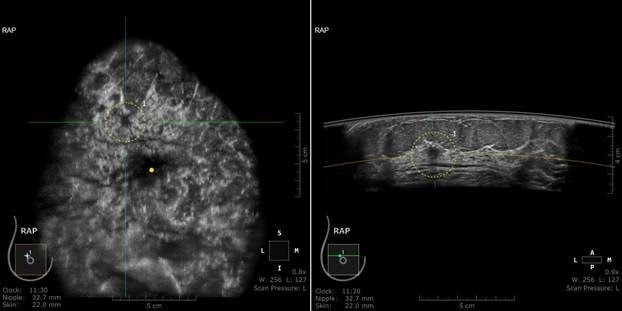

ABD’de, yoğun meme dokusuna sahip kadınları taramaya yönelik FDA onaylı tek bir ultrason teknolojisi bulunuyor, o da GE Sağlık‘ın bu amaç için özel olarak tasarladığı: “Invenia ABUS teknolojisi.” İnceleme yaklaşık 15 dakika sürüyor ve cihaz, kanser ve yoğun doku arasında net bir ayrım yapmak için tüm memenin 3D görüntülerini oluşturuyor.

Jan‘ın radyoloğu olan Dr. Daniel Ha da Jan ile aynı fikri paylaşıyor ve: “ABUS, memeyi mamografi taramasından farklı bir şekilde inceliyor. ABUS, Jan’ın olgusunda yoğunluğun içini görebildi ve 3D mamogramda görülemeyen bir kanseri tespit etti. 3D mamografi, günümüzde mevcut olan en iyi mamografi teknolojilerine rağmen, yüksek yoğunlukta meme dokusunda zorlu bir işlem olmayı sürdürmekte. ABUS, Jan için meme incelemesine yönelik daha kapsamlı bir yöntem sundu.” diyor.